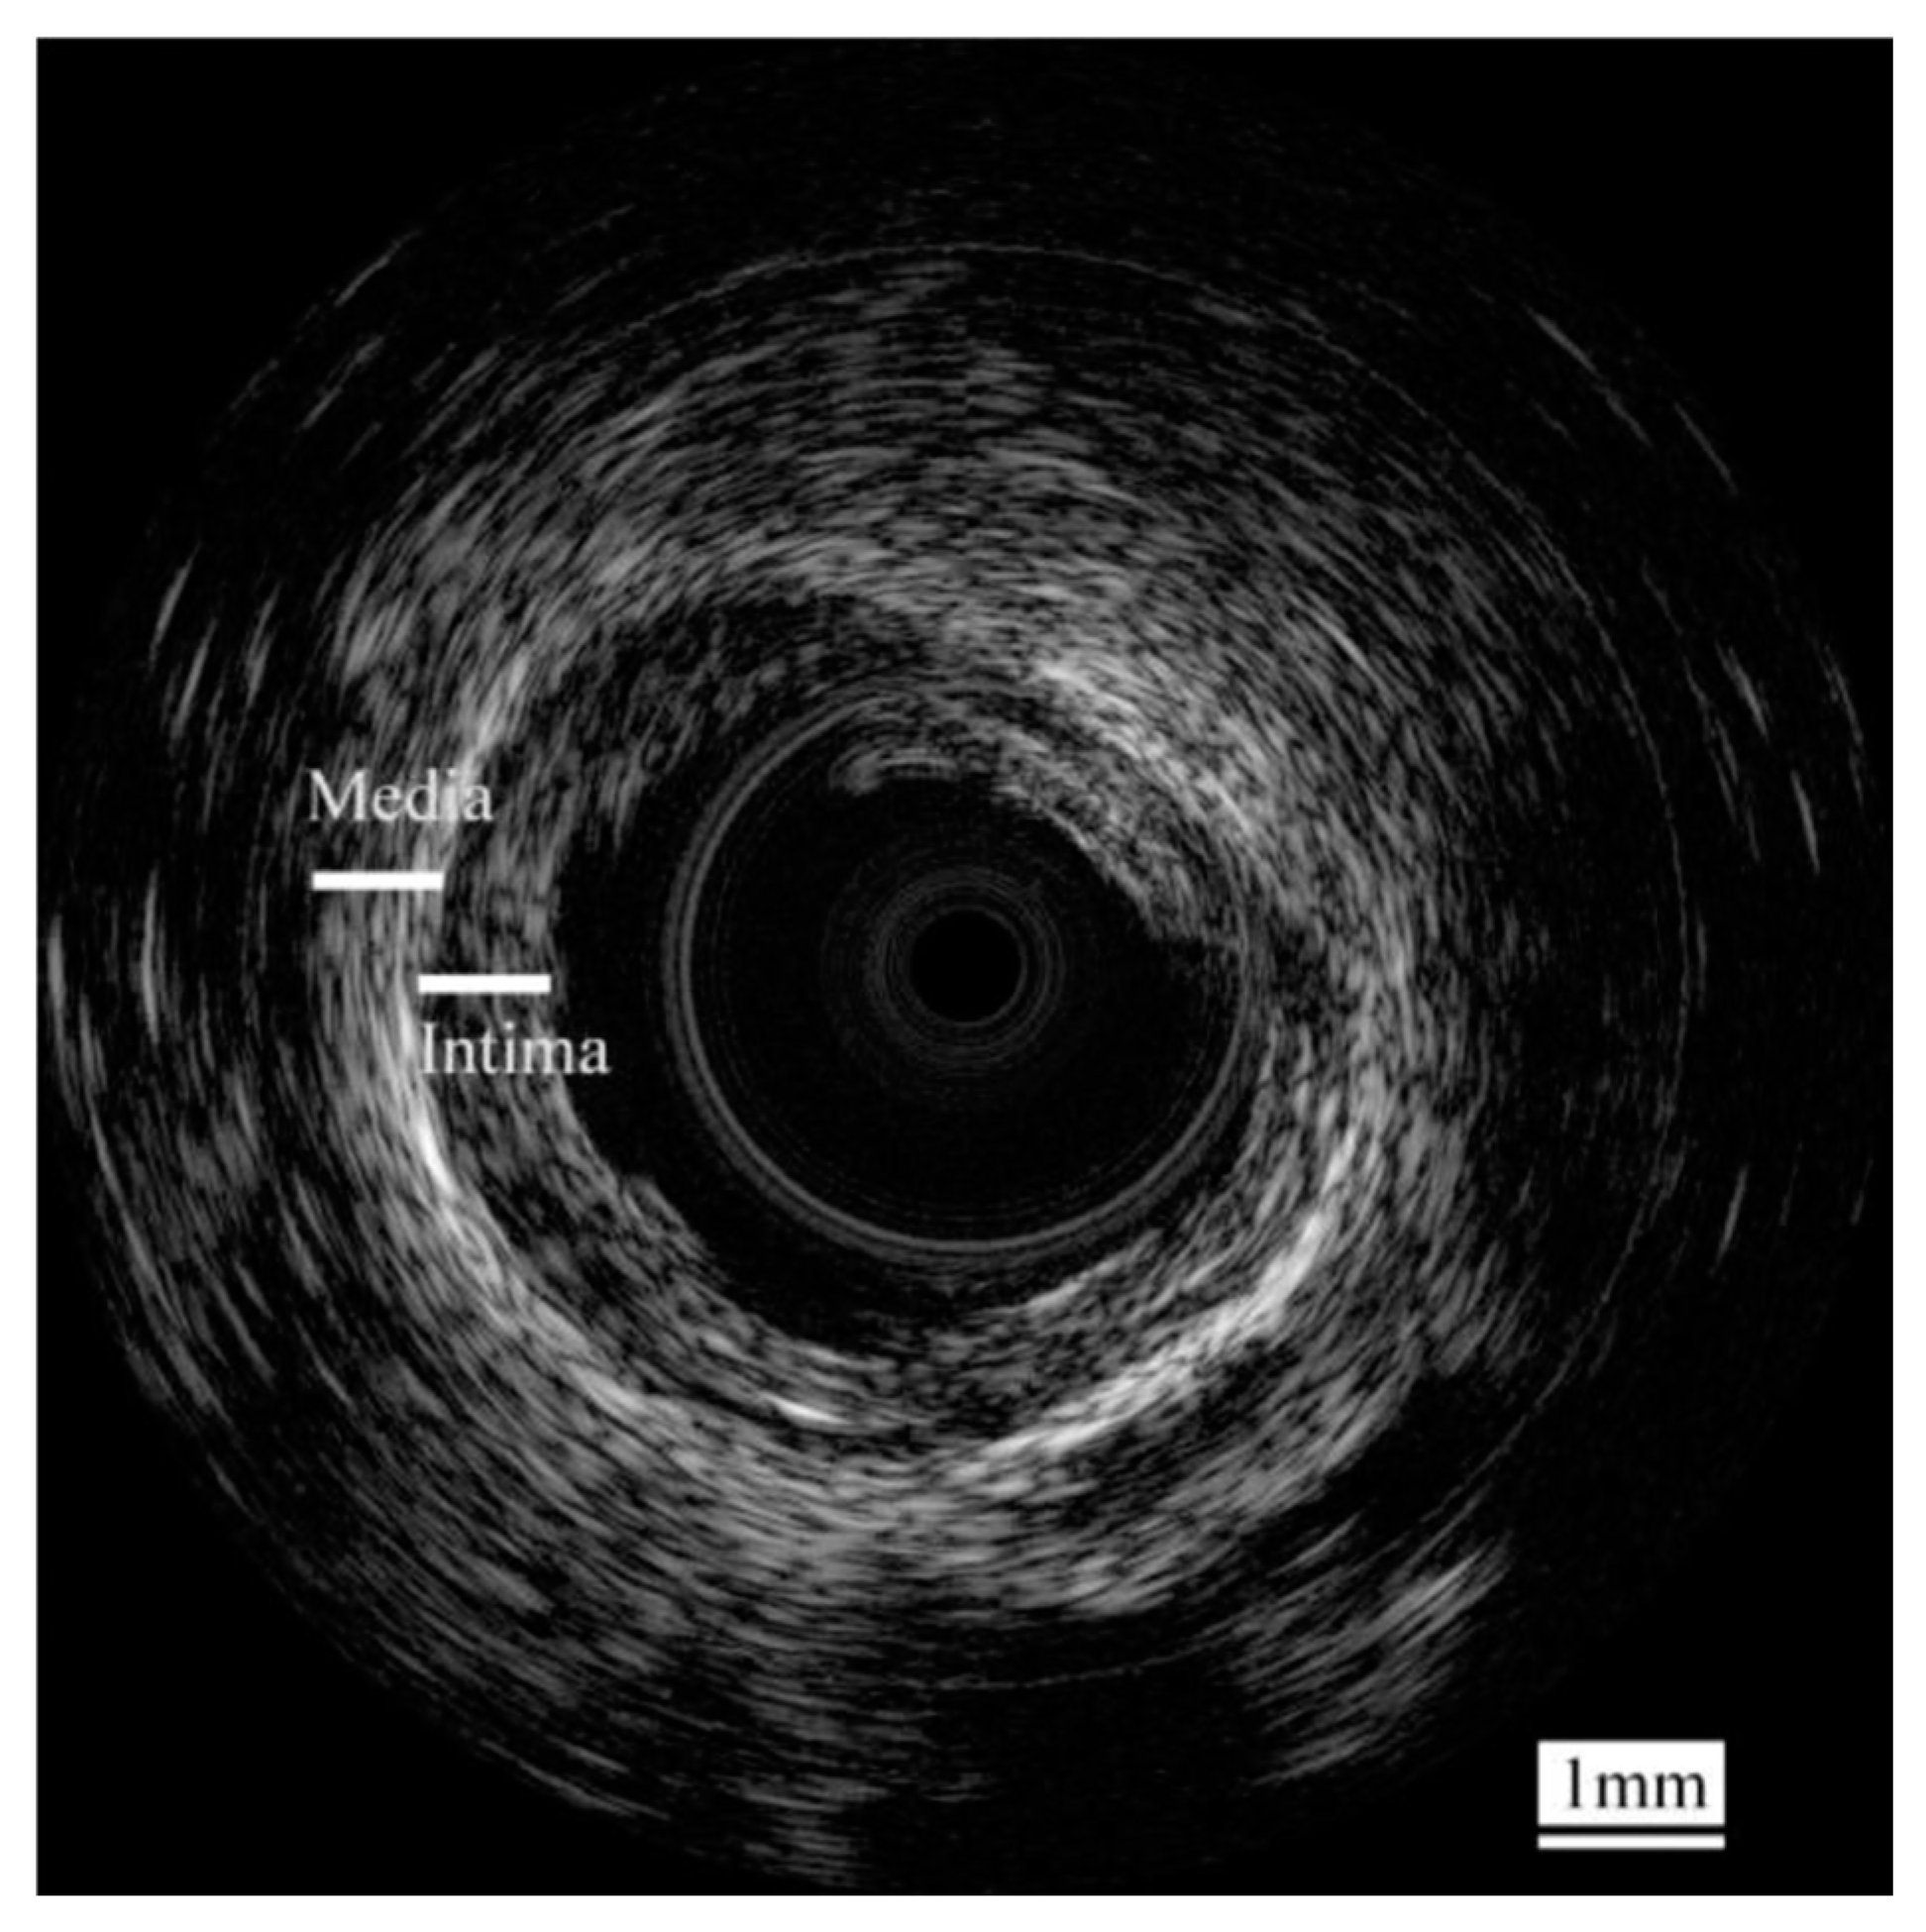

- Yan, X.; Lam, K.H.; Li, X.; Chen, R.; Ren, W.; Ren, X.; Zhou, Q.; Shung, K.K. Correspondence: Lead-free intravascular ultrasound transducer using 0.5BZT–0.5BCT ceramics. IEEE Trans. Ultrason. Ferroelectr. Freq. Control 2013, 60, 1272–1276. [Google Scholar] [CrossRef] [PubMed]